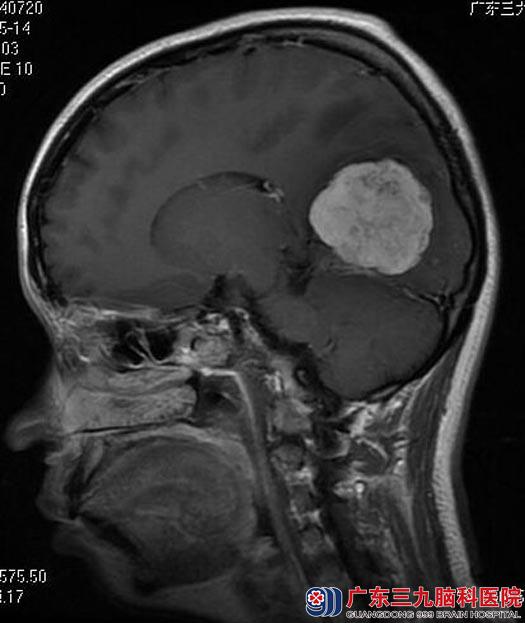

广东三九脑科医院头颅MR提示:右侧枕部镰旁占位性病变,大小约4.6cm×3.0cm×4.4cm,考虑脑膜瘤。这下陈女士更加的恐惧,担心手术后昏迷会成为植物人,家中的幼子从此没有人照顾,等等,

手术前